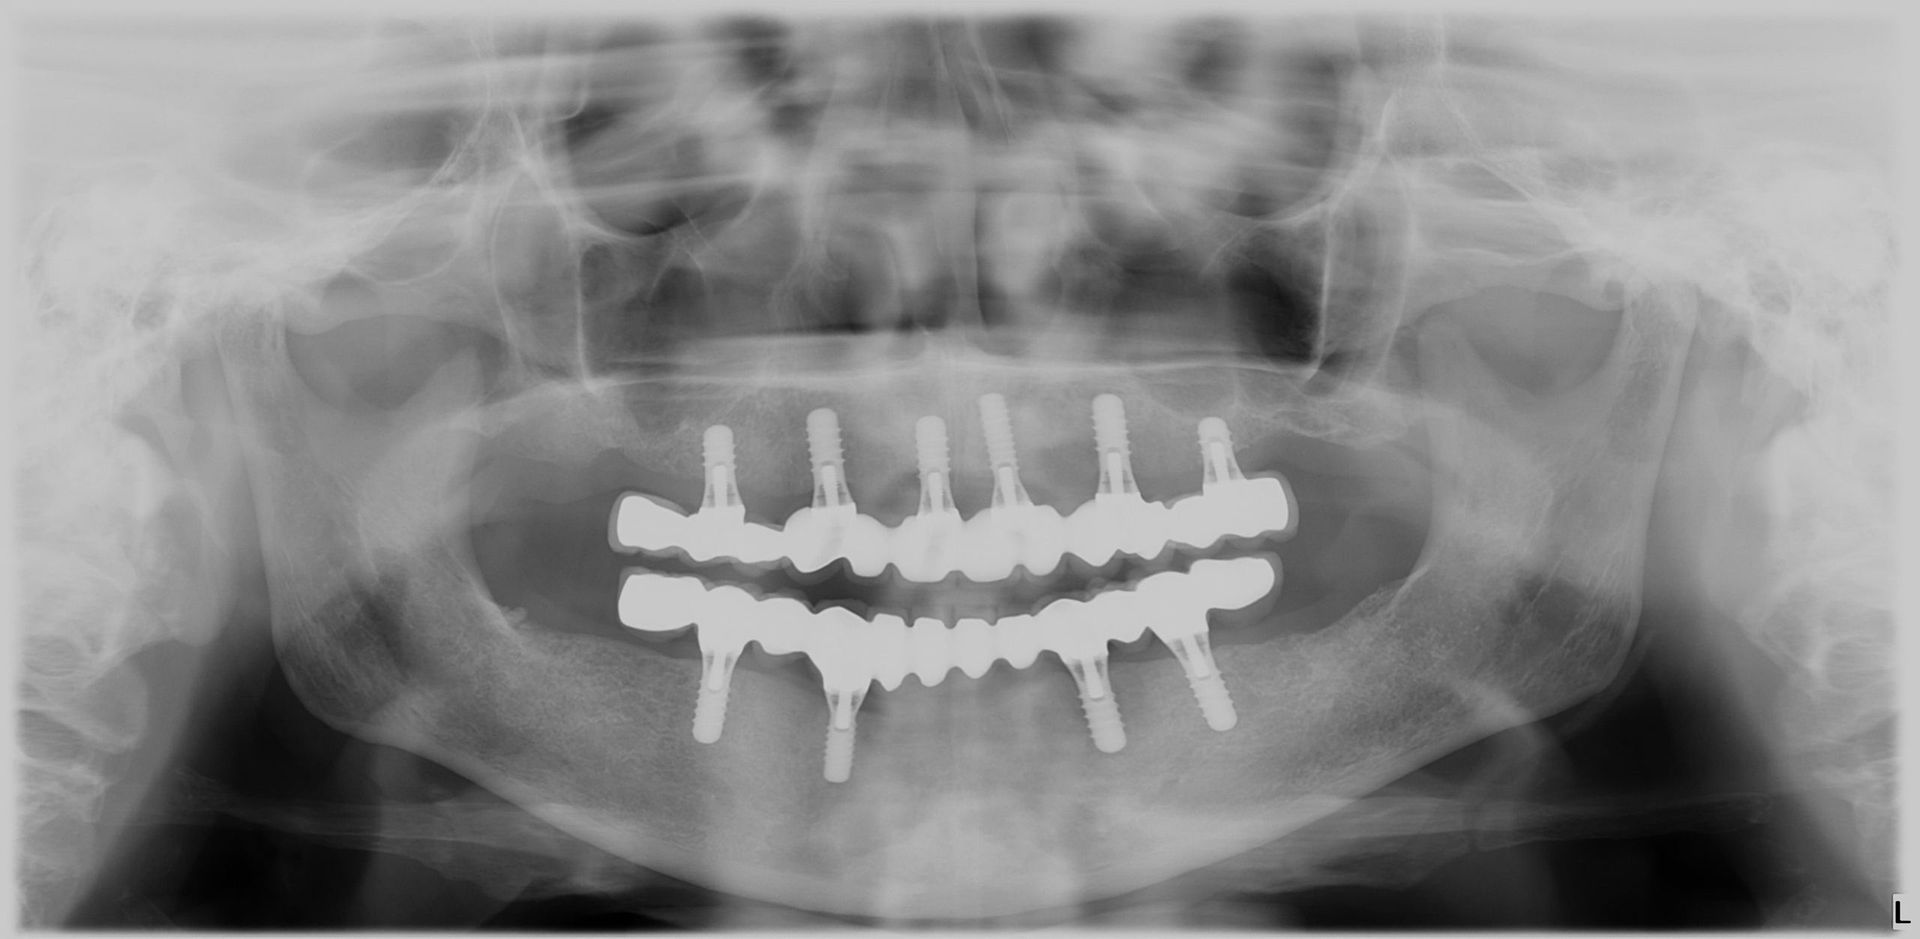

Avant et après implants